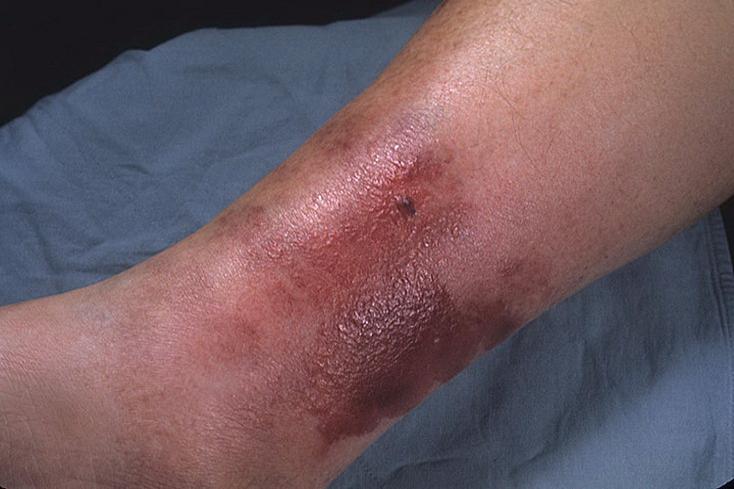

丹毒早期图片

丹毒的潜伏期为2~5天。起初有突然发热、发冷等前驱症状。几个小时到一天后,小腿和面部出现一小块红斑,进行性扩大。典型的皮肤损害是水肿性红斑,边界清楚,表面紧张而有光泽,并迅速向周围扩展。有时在红斑的基础上可出现水疱或血疱。病人经常感到患处灼痛。这种疾病通常在4~5天内达到高峰。感染治愈后,局部可出现脱屑和轻度色素沉着。多发于小腿和头面部,足背部也可发生,多在一侧。